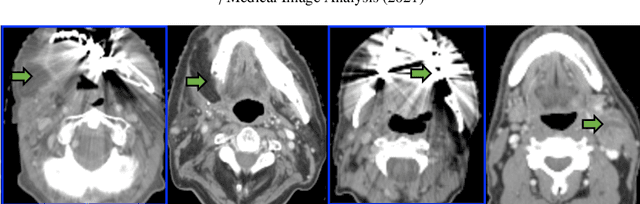

Abstract:Although deep convolutional networks have been widely studied for head and neck (HN) organs at risk (OAR) segmentation, their use for routine clinical treatment planning is limited by a lack of robustness to imaging artifacts, low soft tissue contrast on CT, and the presence of abnormal anatomy. In order to address these challenges, we developed a computationally efficient nested block self-attention (NBSA) method that can be combined with any convolutional network. Our method achieves computational efficiency by performing non-local calculations within memory blocks of fixed spatial extent. Contextual dependencies are captured by passing information in a raster scan order between blocks, as well as through a second attention layer that causes bi-directional attention flow. We implemented our approach on three different networks to demonstrate feasibility. Following training using 200 cases, we performed comprehensive evaluations using conventional and clinical metrics on a separate set of 172 test scans sourced from external and internal institution datasets without any exclusion criteria. NBSA required a similar number of computations (15.7 gflops) as the most efficient criss-cross attention (CCA) method and generated significantly more accurate segmentations for brain stem (Dice of 0.89 vs. 0.86) and parotid glands (0.86 vs. 0.84) than CCA. NBSA's segmentations were less variable than multiple 3D methods, including for small organs with low soft-tissue contrast such as the submandibular glands (surface Dice of 0.90).